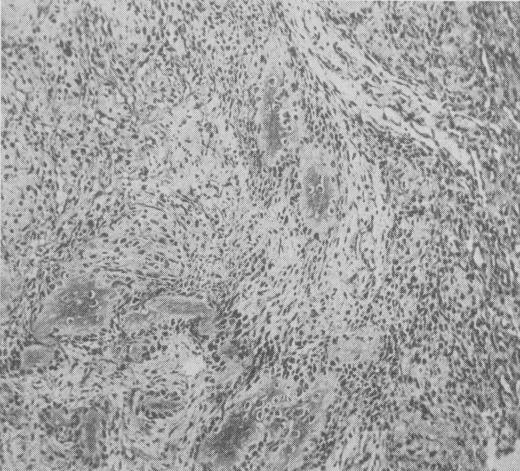

PAROSTEAL OSTEOSARCOMA.

Am Surg. 1964 Nov;30:730-6.